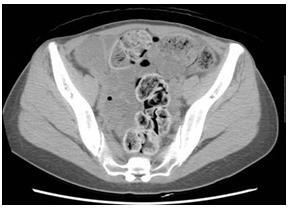

照片4:腹部CT 照片,軸向圖像,盆腔

盆腔左邊的降結(jié)腸中含氣體,看似軟便。腹壁中間為乙狀結(jié)腸,發(fā)白,水分較少,猶如石塊。仙骨前面的直腸存在類似兔子糞便樣的小結(jié)石狀糞便。

照片6:腹部CT

乙狀結(jié)腸出現(xiàn)明顯擴(kuò)張,2周的糞便鑲嵌其中。乙狀結(jié)腸上部將肝下方,胃和橫結(jié)腸向上方擠壓,左側(cè)乙狀結(jié)腸下方可確認(rèn)內(nèi)腔積蓄圓形糞便和氣體。